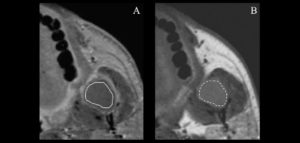

132 – Tratamiento de la reabsorción radicular interna idiopática perforante: controles radiográficos

La reabsorción radicular interna (RRI) es una afección inflamatoria que resulta en la destrucción progresiva de la dentina intra-radicular a lo largo de los tercios